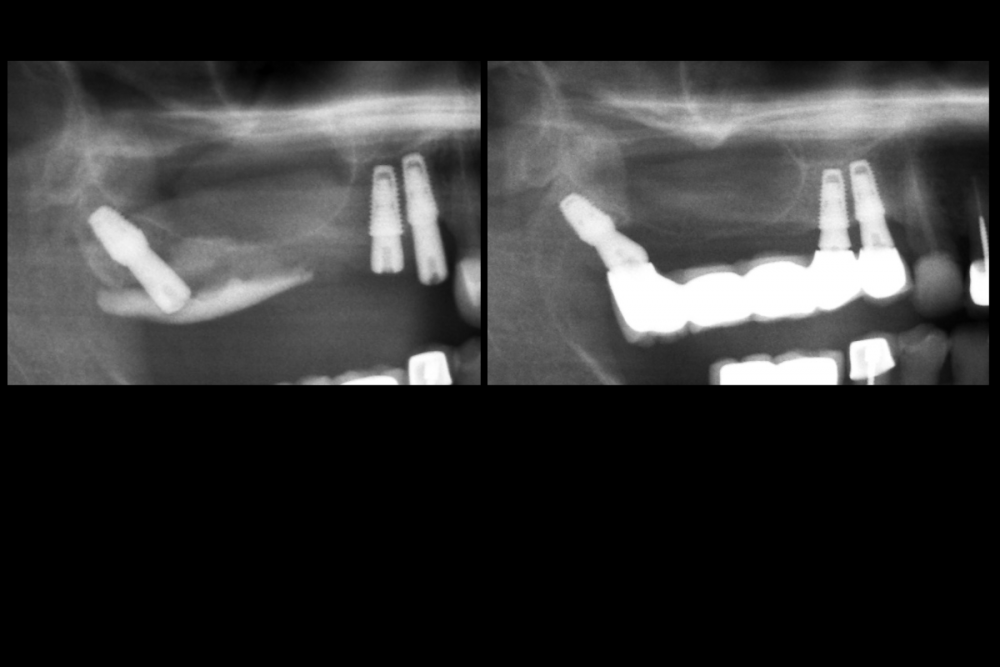

rustam. Опубликовано 1 февраля, 2022 Поделиться Опубликовано 1 февраля, 2022 Мой случай из моей практики 1 1 Ссылка на комментарий

Карен Аванесов Опубликовано 2 февраля, 2022 Автор Поделиться Опубликовано 2 февраля, 2022 я так вижу что был синуслифтинг справа и очевидно не совчем удачный, я не ошибся? Ссылка на комментарий

rustam. Опубликовано 4 февраля, 2022 Поделиться Опубликовано 4 февраля, 2022 Эту имплантацию делал 2014 году, в то время не было опыта делать синуслифтинг и по этому я так обошел пазуху имплантами Ссылка на комментарий